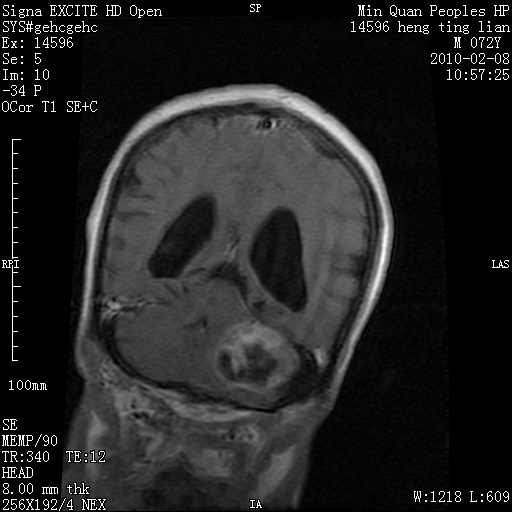

m,72,头疼,头晕两年,伴视力模糊三月,饮食呛咳两天。pe:颈部抵抗,左眼突出,左眼瞳孔约3mm,对光反射消失,双眼失明,伸舌困难,双肺呼吸音粗,心率110次/分,左上肢肌力i级,左下肢屈曲,肌张力高。现有08年2月19mri平扫及10年2月8日mri增强请会诊。ct病灶呈低密度伴散在点、片状等密度区,无明确钙化(无ct片资料可供上传)。[

脑外肿瘤,囊实性,环状不规则强化,内听道扩大,考虑神经源性肿瘤

左侧桥小脑区占位伴梗阻性脑积水----考虑 1神经鞘瘤 2室管膜瘤。

左侧桥小脑区神经鞘瘤伴梗阻性脑积水。

脑外肿瘤,病灶呈匍匐蔓延,表皮样囊肿可能性大。